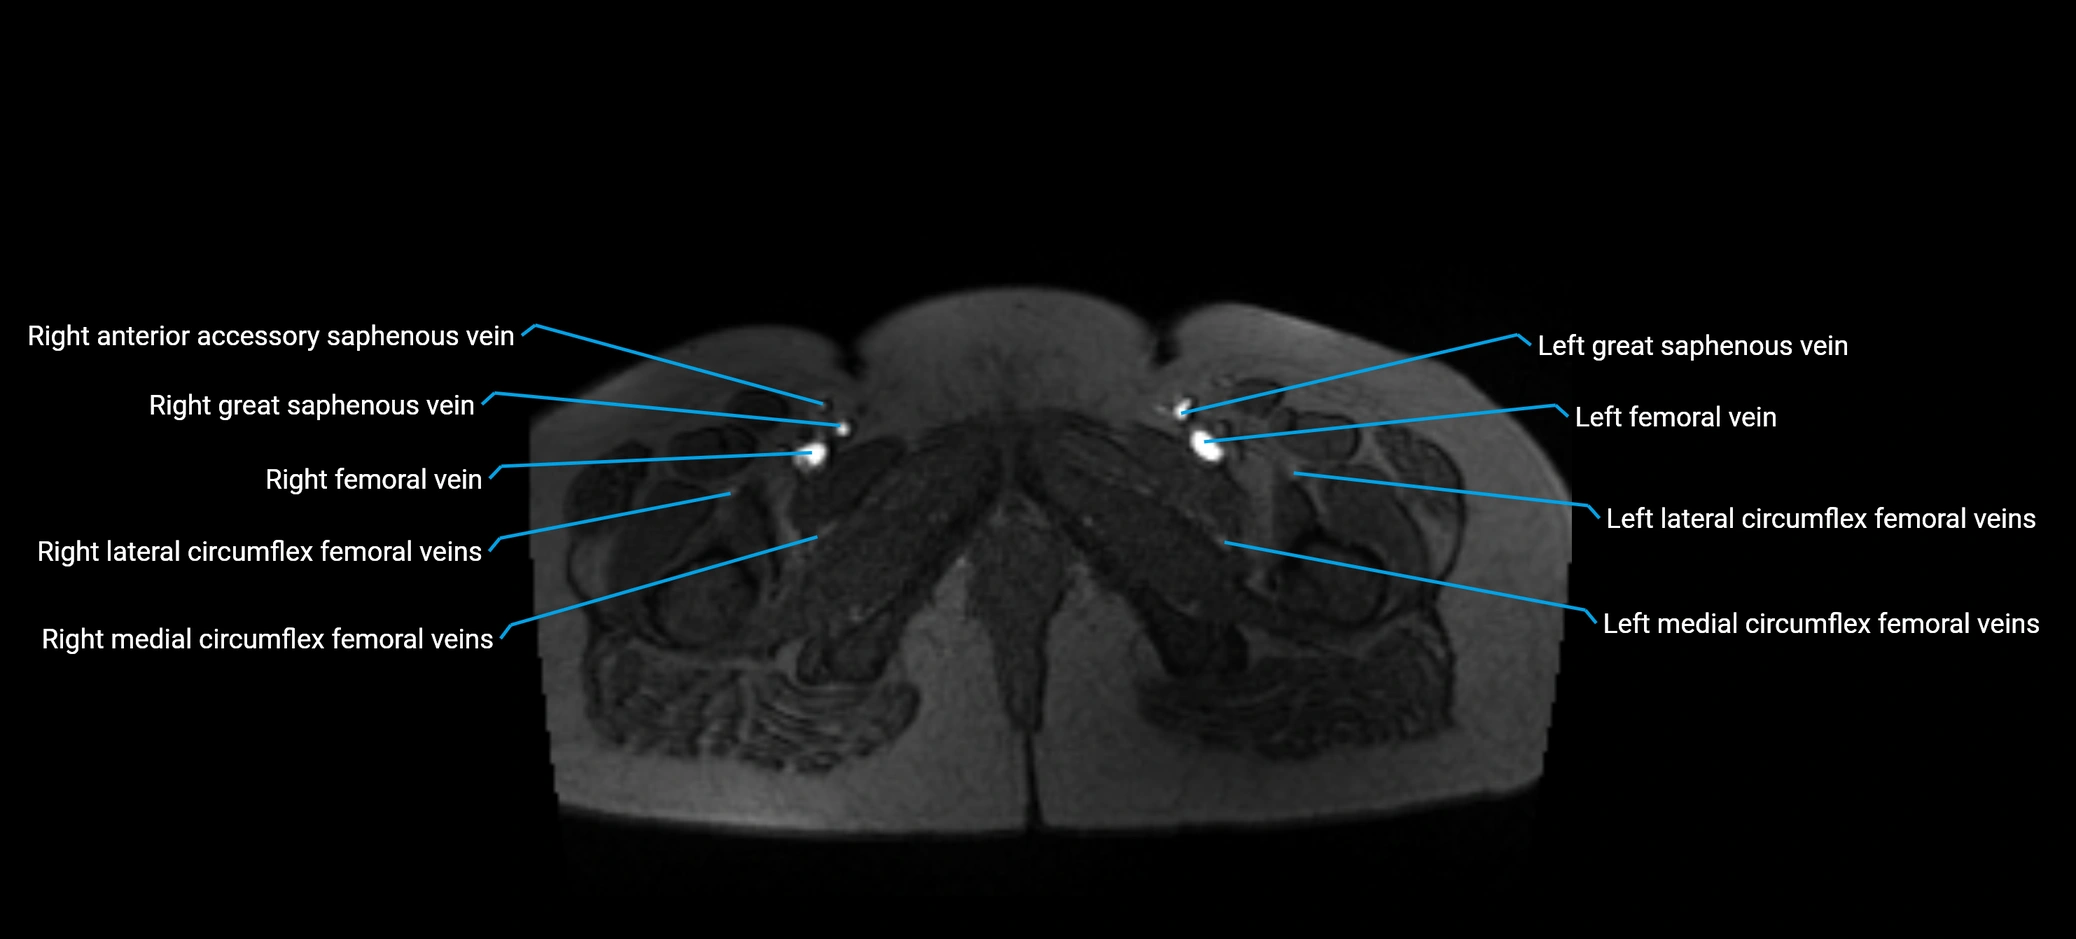

MRI image

image